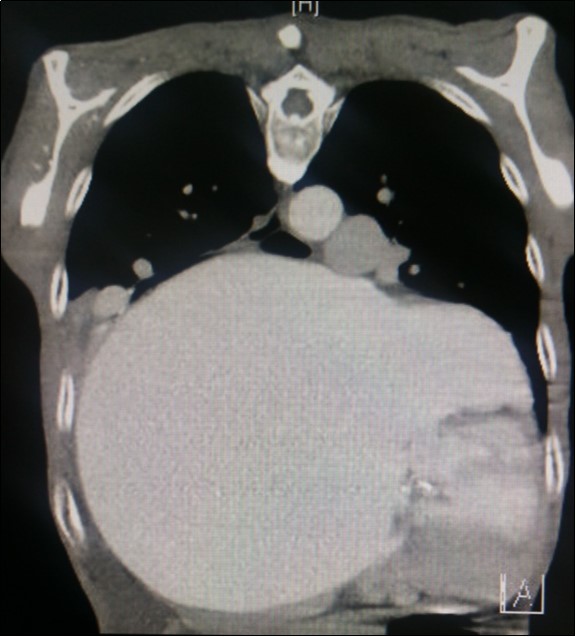

Figure 3.Computed tomography scan (CT) chest AP view, showing the extent of the left atrium filling the left and right hemithoraces.

Computed tomography scan (CT) chest AP view, showing the extent of the left atrium filling the left and right hemithoraces.

A dramatically dilated left atrium was seen on a TTE (see Figure 2a, Figure 2b, Figure 2c, and Figure 2d). Severe mitral stenosis with associated regurgitation was evident, with a mean gradient across the valve of 11mmHg and a hyperdynamic left ventricle. The left atrial volume measured by Simpson’s biplane method (see Figure 2c) was 2108mL, or 1548.5 ml/m2, based on height 1.55 metres and weight 44 Kg. Normal left atrial volume in a woman is 16 - 34 ml/m21. The computed tomography scan (CT) chest AP view (see Figure 3) is also shown.